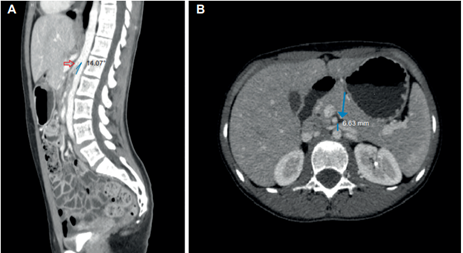

Adicionalmente fue valorada por psiquiatría, conceptuando que cursaba con cuadro ansioso, sin trastornos de la conducta alimentaria. Ante la poca claridad en los estudios, sin hallazgos relevantes en la batería de exámenes de laboratorio clínico, se decidió revisar junto con radiología las imágenes del TC trifásico realizado inicialmente, encontrando dos criterios imagenológicos para el diagnóstico de síndrome de pinza aortomesentérica: un ángulo aortomesentérico de 14,5° y una distancia aortomesentérica de 6,8 mm, asociados a dilatación duodenal leve (Figura 1); que sumados a la sintomatología permitieron hacer el diagnóstico definitivo de síndrome de Wilkie.

Figura 1. Tomografía computarizada de abdomen contrastada. A) Reconstrucción en plano sagital en el cual se aprecia una disminución del ángulo aortomesentérico de 14,5°. B) Reconstrucción en plano axial donde se observa una reducción en la distancia aortomesentérica de 6,8 mm.

Es importante mencionar que en esta imagen se observó también una disminución del calibre de la vena renal izquierda, este hallazgo supuso contemplar la presencia del síndrome de cascanueces o nutcracker de manera concomitante. Dado que no se documentó hematuria, proteinuria, anemia, ni predominio de dolor en flanco izquierdo, no se profundizó en este aspecto y no se consideró necesario realizar otras imágenes para confirmar esta sospecha 7.